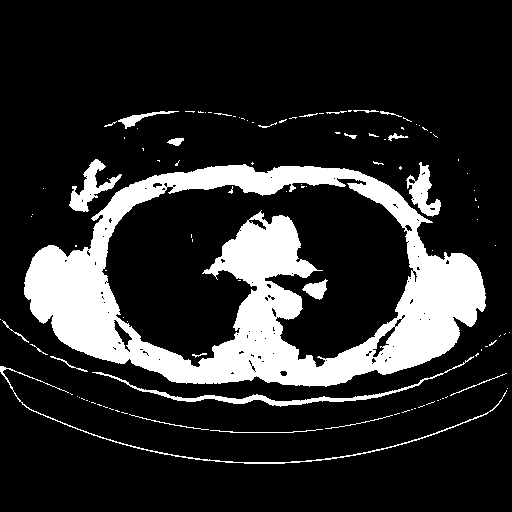

Generated VENOUS CT scan (A→B translation)

Full window (WL 1023.5, WW 4095 β†’ Low βˆ’1024, High +3071)

Actual HU range: [-1024.0, 3071.0]